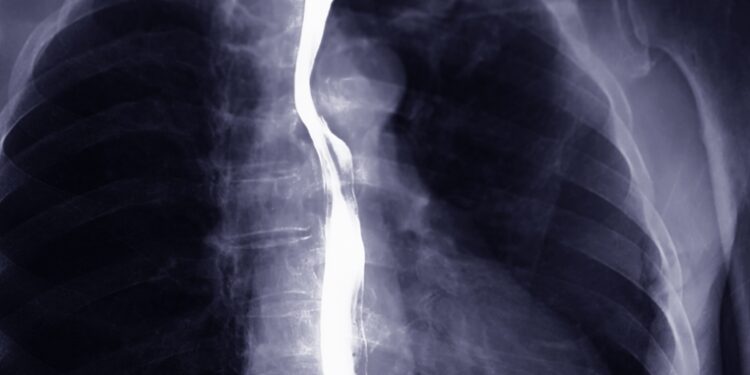

• Stemplės rentgenograma (bario testas): Atliekamas nuryjant specialų skystį ir stebint, kaip jis juda stemple. Taip galima aptikti tiek plėveles, tiek kitus susiaurėjimus.